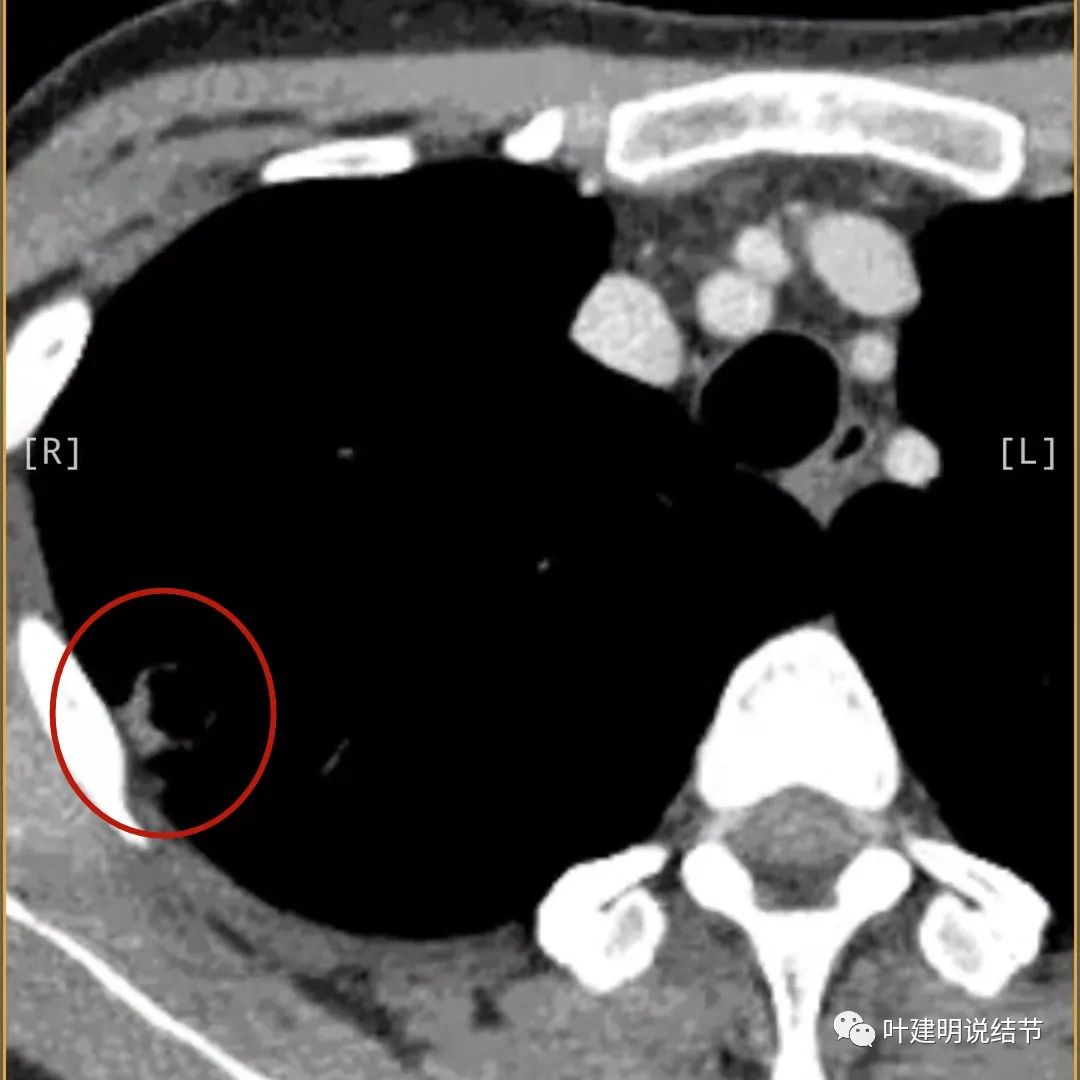

邻近胸膜明显增厚,且广基底,主病灶前方有小片磨玻璃影

主病灶与胸膜间基本相连,模糊清(蓝色箭头),主病灶壁厚薄欠均,边上有高密度条索状(桔色箭头)

主病灶不见了的层面,仍有边上高密度条索状的影像,邻近胸膜仍有异常(蓝色箭头)